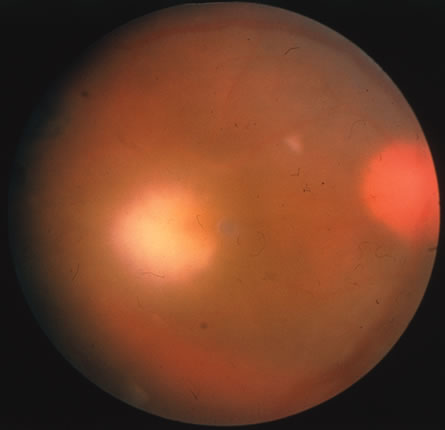

In primary ocular HSV infections, a severe follicular conjunctivitis with regional adenopathy is present. Vesicles may appear on the eyelid skin or lid margin, producing blepharitis (Fig. 3). Corneal involvement initially takes the form of a superficial punctate keratitis, which may progress to dendritic or geographic ulceration. Stromal infiltrates and uveitis are less common and relatively mild in primary disease. In uncomplicated cases, lesions usually heal completely in 2 to 3 weeks without scarring. Most cases of ocular HSV are recurrences. Recrudescent ocular herpes may take the form of dendritic or geographic ulcers, recurrent erosions, interstitial or disciform stromal keratitis, and anterior uveitis.3 HSV may also be an agent of retinitis and acute retinal necrosis (Fig. 4).